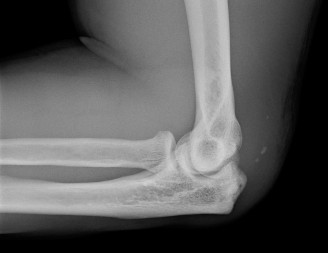

A 23-year-old, semi-professional football linebacker presents with left elbow pain after a game. He extended …